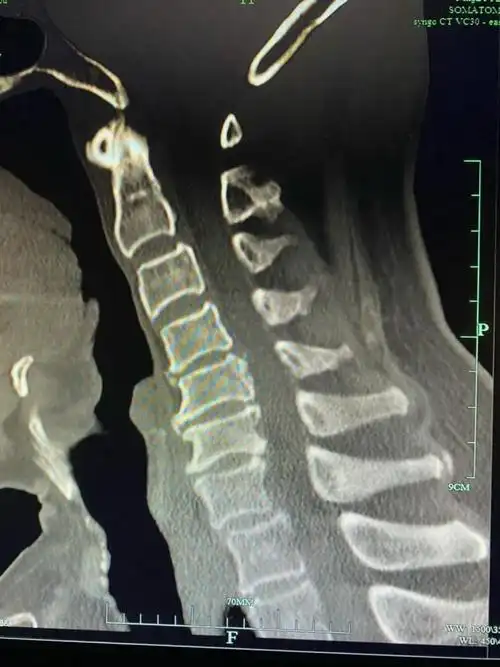

颈椎ct示:颈4-5骨赘增生严重颈椎侧位片示:颈椎生理曲度消失,反弓术中